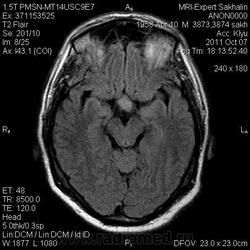

Аденома гипофиза

Вот такая аденома гипофиза сегодня.Мужчина с жалобами на снижение зрения.

Мне кажется что это все же не аденома, может глиома хиазмы ? (воронки гипофиза)? Или еще какое-нибудь объемное образование.... Что то меня смущает, еще не поняла что, но В любом случае наверное я бы однозначно не писала что это аденома, а выставила бы весь диф. ряд.

Танюша, обычно пишем "образование хиазмально-селлярной области"

Присоединяюсь к последнему коментарию, все таки откуда растет по моему мнению трудно однозначно сказать, лучше себя обезопасить написав "объемное образование хиазмально-селлярной области"